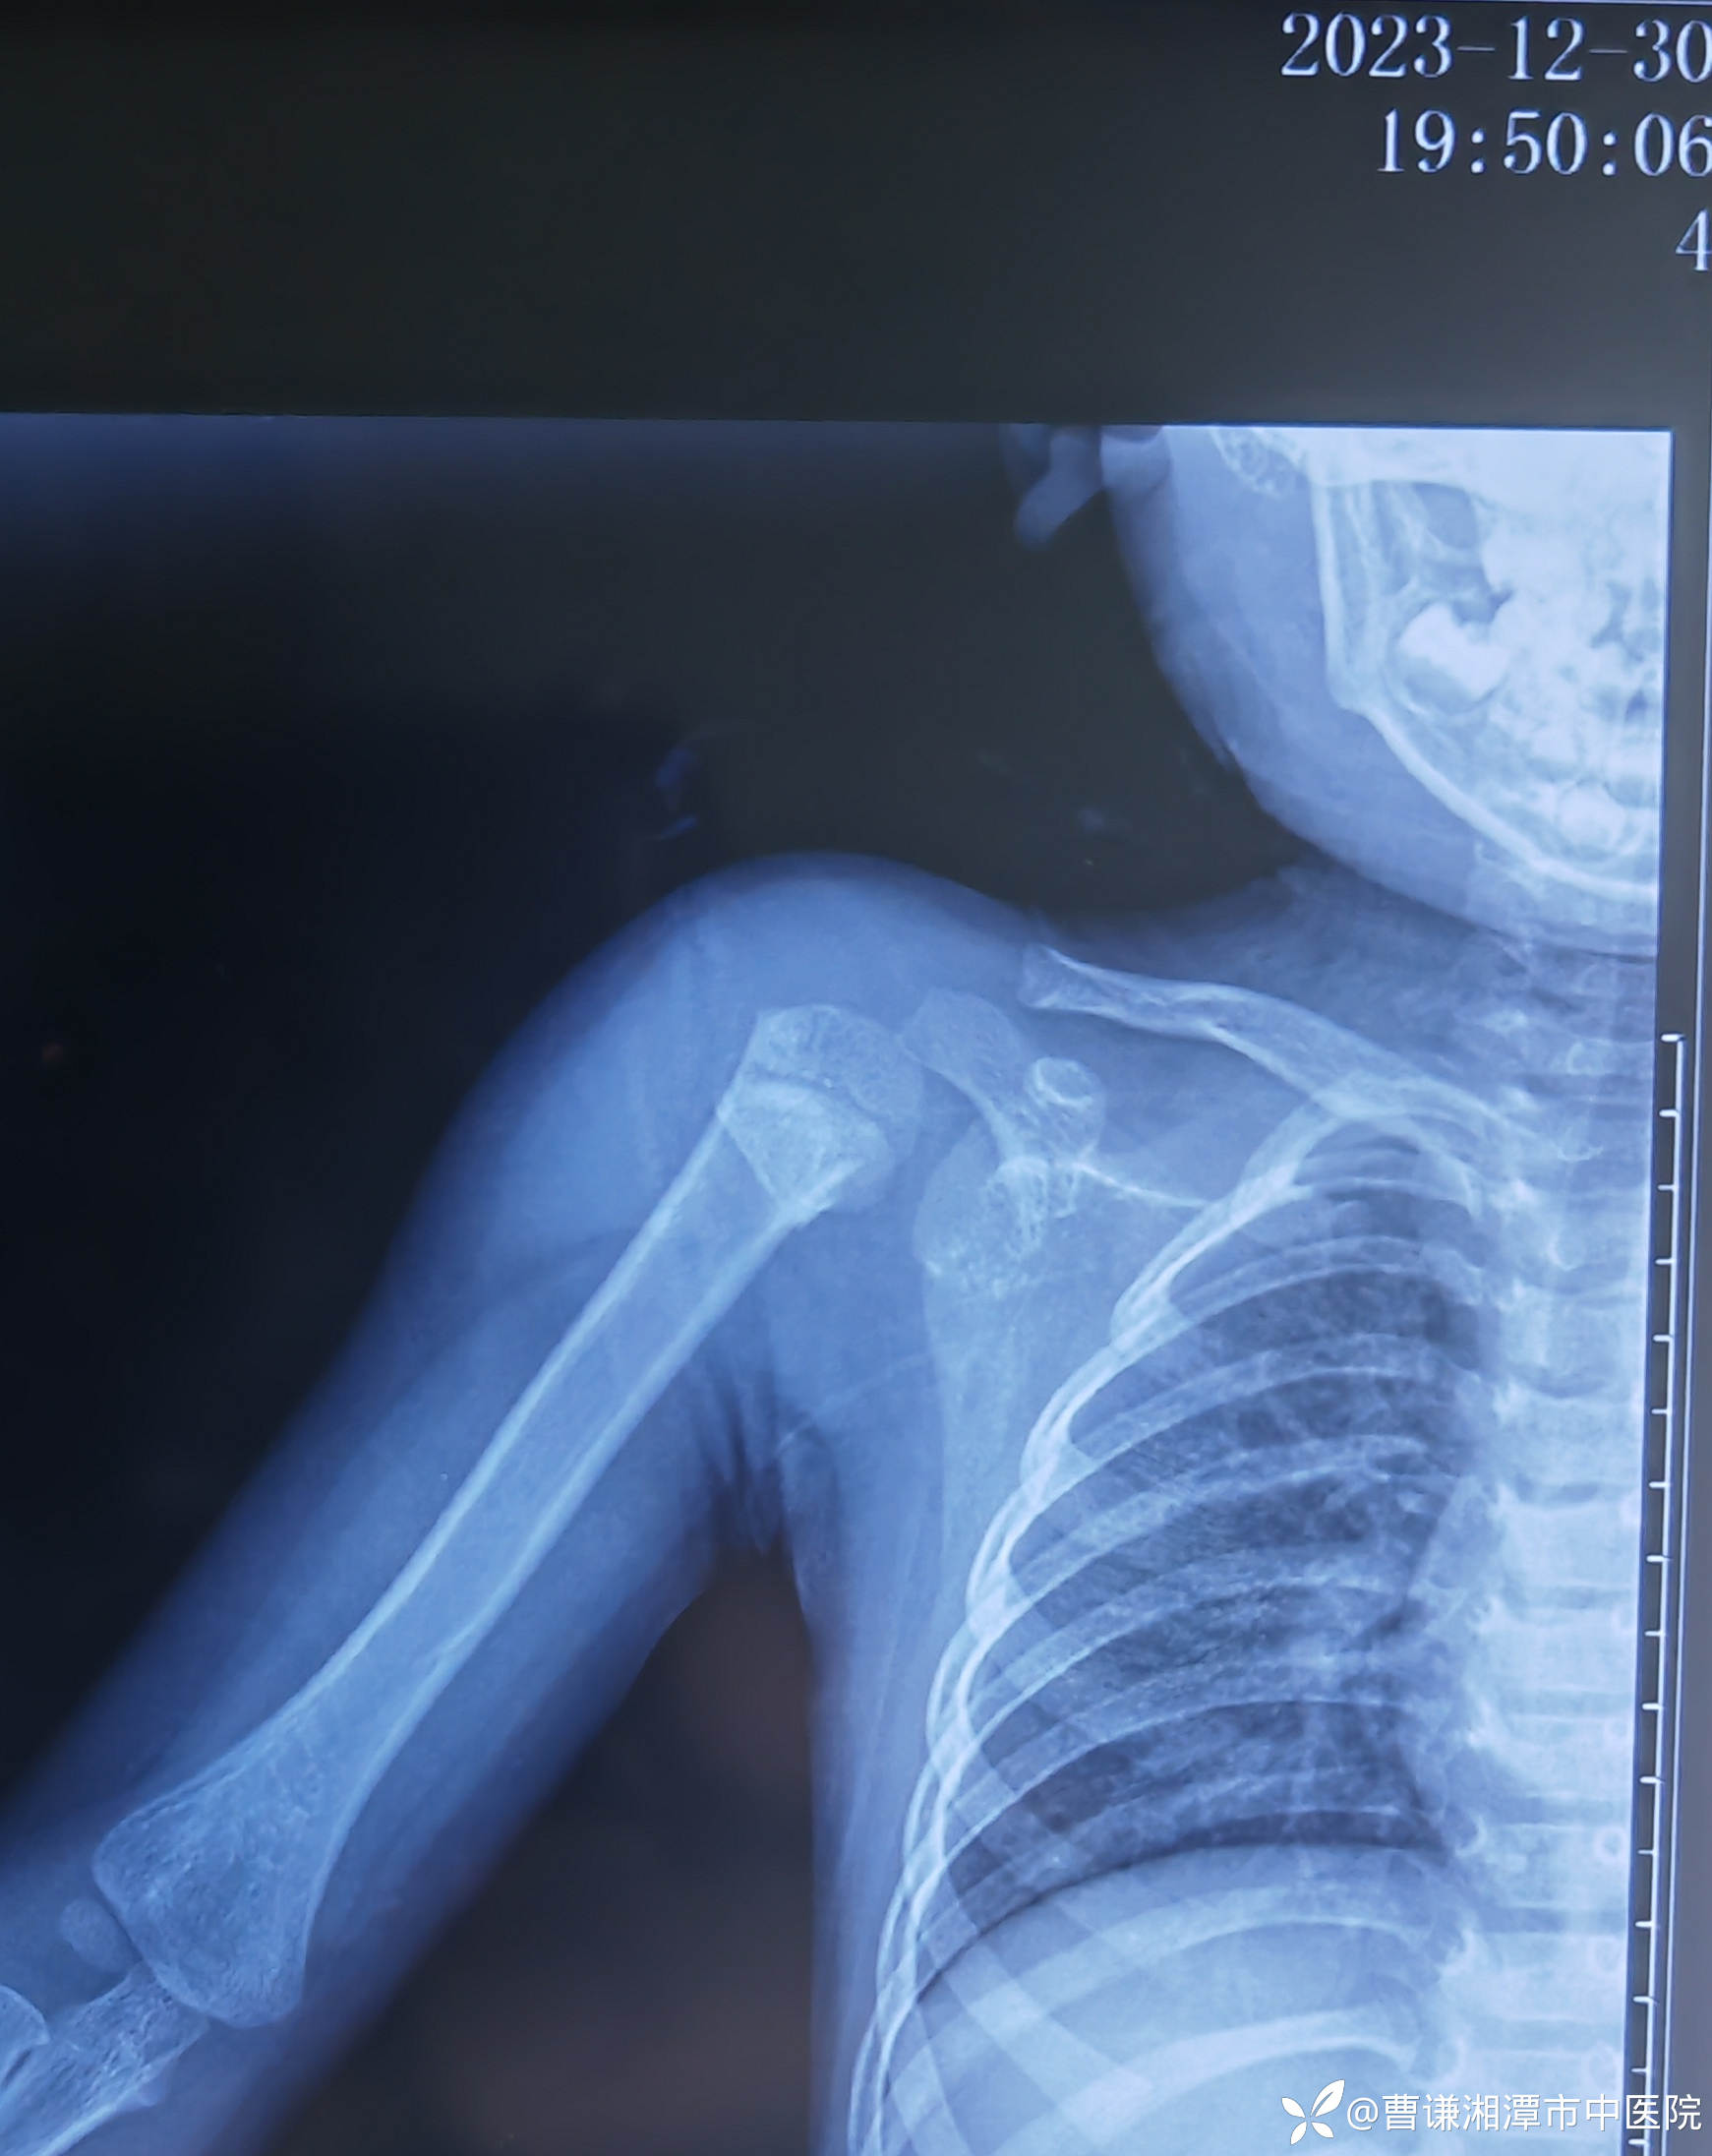

当地医院予以石膏固定转来我院,来我院拍片复查示:远折端向前、向内、向上移位明显,石膏固定显然是无效的,因为患者夜间一直诉疼痛,良好的外固定应该是可以让患者基本无痛的。

未做刻意复位,稍行屈肘牵引,断端前后对向挤压后予以外敷膏药,四块小夹板外固定,前、后方夹板采用医用胶布经肩关节上方进行紧缩固定,前、外、后方夹板再采用医用胶布经肩关节外侧进行紧缩固定,这样使肩关节与躯体成为一个整体。